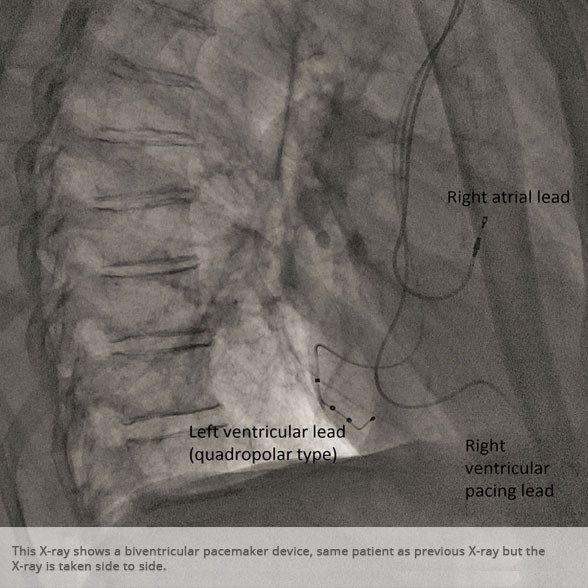

Biventricular pacemaker device Biventricular pacemaker device

BI-VENTRICULAR PACEMAKERS

Bi-ventricular pacemakers are used for the treatment of suitable patients with heart failure who are already on medication but who suffer from a lack of synchrony between the right and left ventricular contraction. This is most commonly caused by an electrical delay (left bundle branch block LBBB) in transmission of signals to the main pumping chamber (called the left ventricle) and is relatively common in patients with advanced heart failure. This delay process commonly worsens the symptoms of heart failure and it is not generally influenced by medication alone.

Although not all patients universally respond to bi-ventricular pacing (or cardiac resynchronisation therapy/CRT), patients with more advanced dys-synchrony tend to experience remarkable improvement. Bi-ventricular ICDs have the additional benefit of recognising life threatening arrhythmia and deliver both fast pacing bursts or shocks to restore normal heart rhythm.